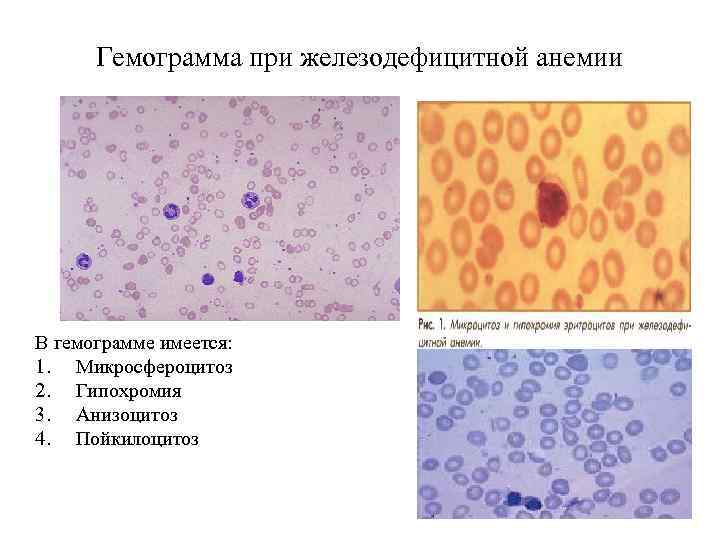

Гемограмма при железодефицитной анемии В гемограмме имеется: 1. Микросфероцитоз 2. Гипохромия 3. Анизоцитоз 4. Пойкилоцитоз

Гемограмма при железодефицитной анемии Признаки гипохромной микроцитарной анемии, снижение концентрации гемоглобина. Количество эритроцитов вначале может быть нормальным. При значительном дефиците железа оно также снижается, но в меньшей степени, чем уровень гемоглобина, низкий цветовой показатель (0, 7 -0, 5) и уменьшение средней концентрации гемоглобина в эритроцитах. Уменьшаются размеры эритроцитов (микроцитов) и их насыщенность гемоглобином (гипохромия). В мазках крови преобладают небольшие гипохромные эритроциты, аннулоциты (эритроциты с отсутствием гемоглобина в центре, в виде колец), эритроциты неодинакового размера и формы (анизоцитоз, пойкилоцитоз). При тяжелых анемиях могут появляться отдельные эритробласты. Количество ретикулоцитов не изменено. Только при анемии, развившейся на фоне кровопотери, непосредственно после кровотечения количество ретикулоцитов повышается, что является важным признаком кровотечения. Количество лейкоцитов имеет нерезко выраженную тенденцию к снижению. Лейкоцитарная формула мало изменена. Количество тромбоцитов остается нормальным, а при кровотечениях несколько повышено